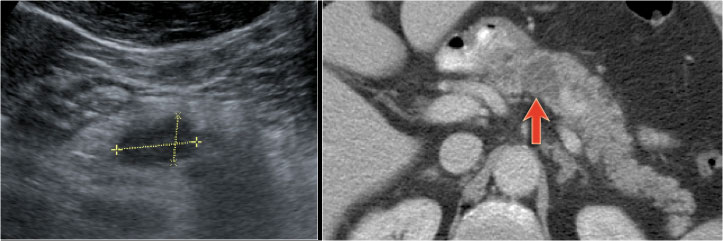

CT-images of an IPMN with a dilated pancreatic duct (blue arrows).

Notice enhancing solid nodule in the pancreatic head (red arrow).

Continue with the ultrasound-image.

The US-image shows a large branch-duct component within the pancreatic head.